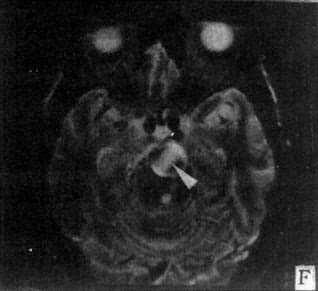

MRI不需注射造影剂便能直接观察动脉瘤的瘤壁和瘤内血栓(图5-1-6E、F)、血管畸形的供血和引流血管、畸形血管团以及继发性改变,例如脑出血、缺血和软化等情况。但动脉瘤和血管畸形在手术前一般还需作脑血管造影或DSA,以便详细了解脑的供血和脑循环情况。

图5-1-6 MRI扫描SE序列图像

在矢状面(A)和冠状面(B)T1WI可见垂体肿块向鞍上延伸,呈等信号区(→);在横断面T1WI(C)和T2WI(D)上分别可见左枕和右基底节区脑梗塞灶呈低和高信号区(→);在矢状面T1WI(E)和横断面T2WI(F)上,可见基底动脉瘤环形影,其内为低信号和高信号区,高信号区为瘤内血栓形成(→)